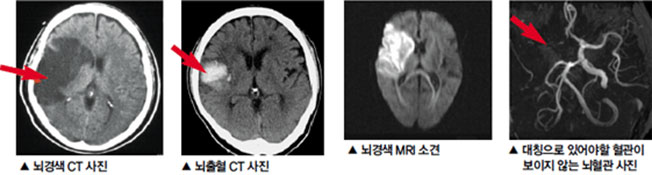

이번 포스팅에서 뇌경색 초기증상 모두 알아보려고 해요. 한 번쯤은 뇌경색, 뇌출혈, 뇌졸중에 대해서 들어보신 적이 있을꺼에요.

뇌경색 치료 방법

뇌경색 초기증상이 의심된다면 지금 바로 병원을 내방해 진단을 받고 적절한 치료를 손대는 것이 후유증을 감하는데 중요 해요. 시간이 관건이며, 뇌세포의 괴사, 증상 악화, 너무 늦으면 사망에 이를 수 있는 뇌혈관의 괴사를 피하기 위하여 증상이 나타난 뒤에 4시간 이내에 잘 맞은 약물, 시술 또는 수술을 신속히 실시해야 합니다. 치료로 즉시 하셔야 해요.